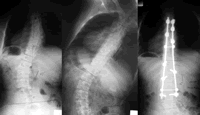

青少年特发性脊柱侧凸(AIS)是10岁以上儿童在发育成熟前常见的一种非先天性脊柱畸形,2%~3%的青少年有此畸形,其占全部脊柱侧凸病例的80%。由于脊柱侧凸、扭曲和胸廓变形会直接影响患者的外观、心肺功能和生活质量,并严重危害他们的身心健康,因此,应重视AIS的早期诊断和治疗,尽早矫正畸形。

AIS的治疗方案包括非手术治疗和手术治疗,一般将侧凸的冠状面Cobb角是否超过40°作为是否选择手术治疗的决策依据。

临床上通常根据冠状面的Cobb角、骨骼发育情况、脊柱矢状面变化、椎体旋转程度及侧凸的自然病史判断是否需手术治疗。一般认为,对处于生长期、Cobb角>40°、非手术治疗无效(6个月内侧凸进展超过5°)、伴有疼痛、胸椎前凸及伴明显外观畸形的患者应选择手术治疗 ......